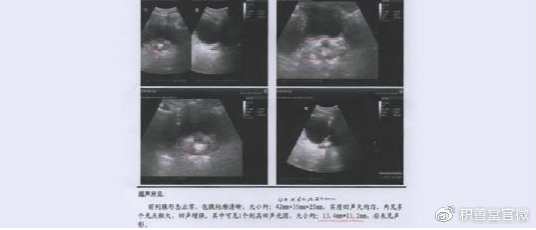

2020年7月,田某返回来继续治疗,蔡主任给他把脉,发现他的腺体病变有了明显的改善,他的腺体还是膨大,但病灶也开始膨松变大。

蔡主任指出:腺体膨大是因为病灶开始膨松变大,导致腺体体积明显改变。病灶膨松变大说明药力已经渗透到了病灶内部,本来坚硬的病灶开始变得疏松才会出现膨大。这说明病灶得到改善,开始被激活,也说明治疗方案正确。

他的腺体还有钙化病灶,但已经只有4mm左右,能崩解和激活的病灶已经基本完成了崩解和激活,这4mm左右的病灶是疾病留下的疤痕,不影响腺体正常功能,所以不必继续崩解,可以停止治疗了。